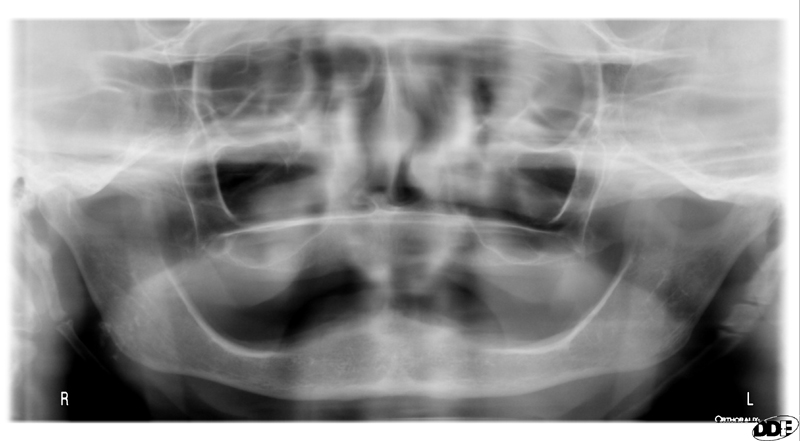

1 / 25

1. (Select ONE OR MORE correct answers)

The radiograph shows evidence of